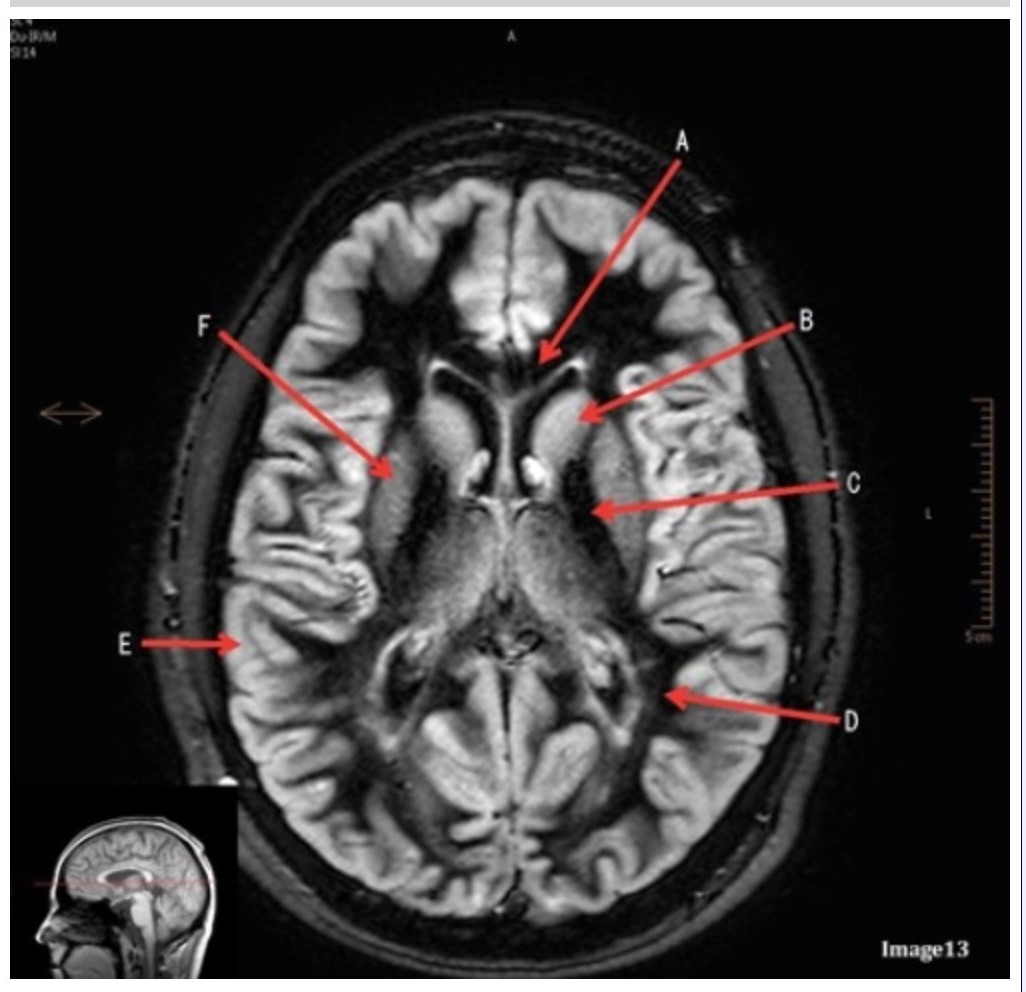

Letter E in Image 13 is pointing to:

A. Grey matter

B. White matter

C. Lentiform nucleus

D. Caudate nucleus

E. Internal capsule

Letter B in Image 13 is pointing to:

A. Splenium of the corpus callosum

B. Genu of the corpus callosum

C. Lentiform nucleus

D. Caudate nucleus

E. Internal capsule

Letter F in Image 13 is pointing to:

A. Grey matter

B. White matter

C. Lentiform nucleus

D. Caudate nucleus

E. Internal capsule

Letter D in Image 13 is pointing to:

A. Grey matter

B. White matter

C. Lentiform nucleus

D. Caudate nucleus

E. Internal capsule

Letter C in Image 13 is pointing to:

A. Splenium of the corpus callosum

B. Genu of the corpus callosum

C. Lentiform nucleus

D. Caudate nucleus

E. Internal capsule

Image 9 is an example of a _____ weighted sequence acquired in the _______ scan plane.

A. T1; Axial

B. T2 FLAIR; Sagittal

C. T2; Axial

D. T2; Coronal